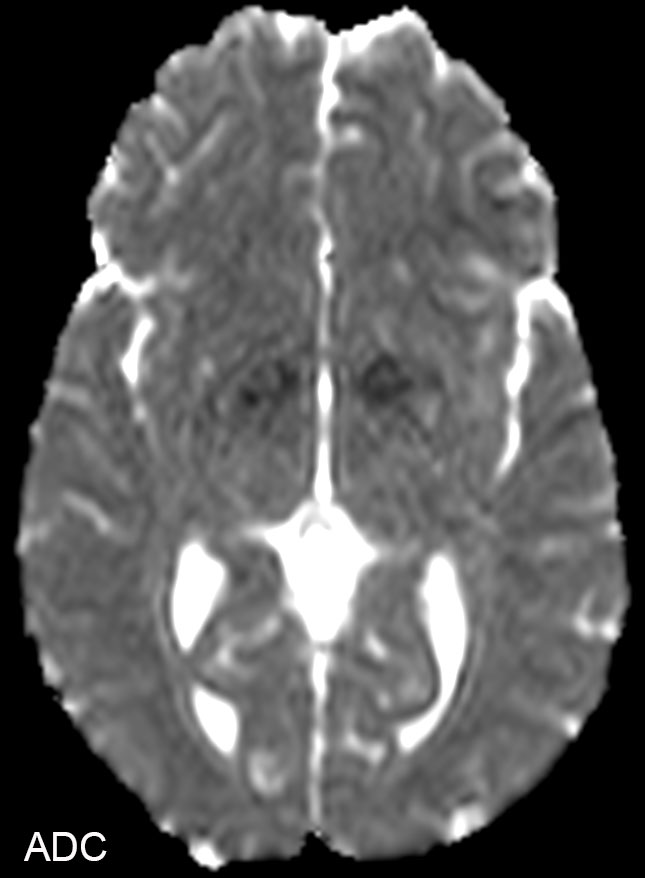

Brain imaging using ComforTone